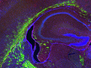

Executing a slick move on the training pitch is one thing, but doing it during a big match is another. And getting treatments working in lab experiments doesn’t mean they’ll be effective in the body. Researchers know that γδ T cells (a type of immune cell, green) have the potential to fight cancer (blue), pinpointing tumour cells that produce stress-induced signals. Triple-negative breast cancer, however, employs a pool of cancer stem cells to evade these immune cells. In lab tests, T cells from healthy donors were able to target these stem cells, but when the researchers repeated the test in mice it was as if they vanished into the crowd, rendering the γδ T cells ineffective. Treating the mice with zoledronate – a drug already used to treat osteoporosis – helped the T cells lock onto the cancer cells, suggesting new combination immunotherapy approaches for the hard-to-treat triple negative breast cancer.